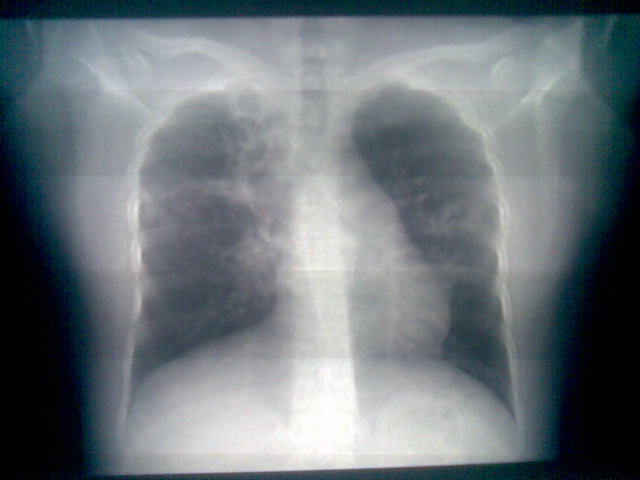

两上肺均见有斑片条结及蜂窝状环状低密度影,以右侧居多,考虑肺结核并支扩可能。

支扩并感染,结核不能排除,建议结合实验室检查或痰检。